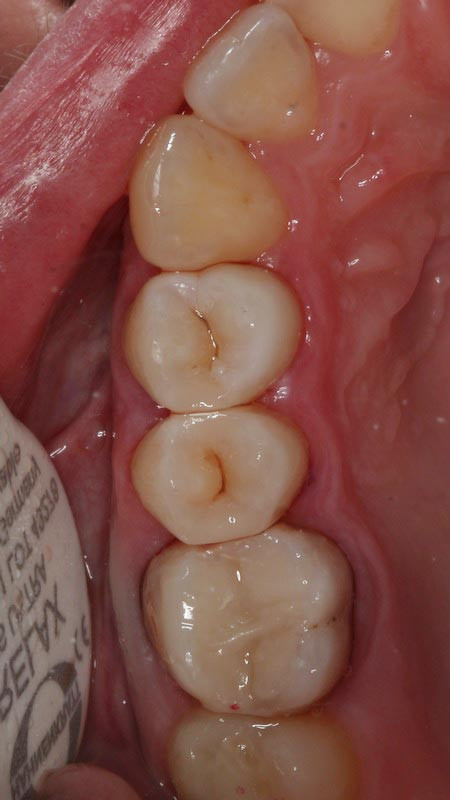

4 работы в портфолио

Врач Сакзлян Вардан Абраамович принимает в стоматологическом комплексе ПРЕЗИДЕНТ в Москве. Имеет рабочий стаж 10 лет. Специализируется на терапевтии и гигиене полости рта, по которым клиника оказывает 6 услуг. Имеет 4 работы до/после в портфолио. Квалификация специалиста подтверждена 17 лицензиями, сертификатами и наградами. Для уточнения дополнительной информации о специалисте или записи на прием можно позвонить по телефону